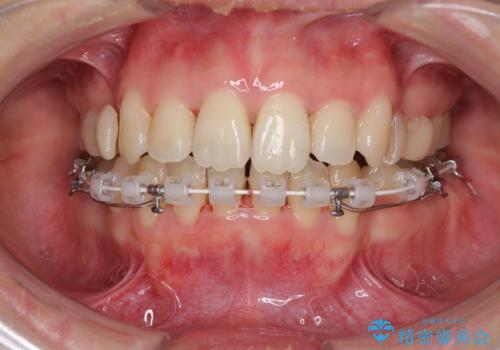

Eラインを改善したい ハーフリンガルによる抜歯矯正

- 矯正装置

- ハーフリンガル

- 口元の突出感を気にして来院された患者様です。

上下左右の第一小臼歯4本を抜歯して口元を下げる治療計画としました。